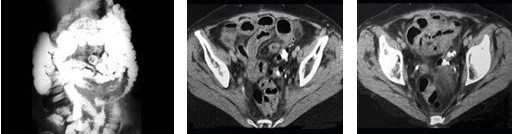

女,43岁,发现盆腔包块3年,排尿困难6日,影像检查如图,最可能的诊断是( )

A:腹腔脂肪肉瘤

B:腹腔恶性间质瘤

C:腹腔畸胎瘤

D:腹腔畸胎瘤伴卵巢内胚窦瘤

E:卵巢内胚窦瘤